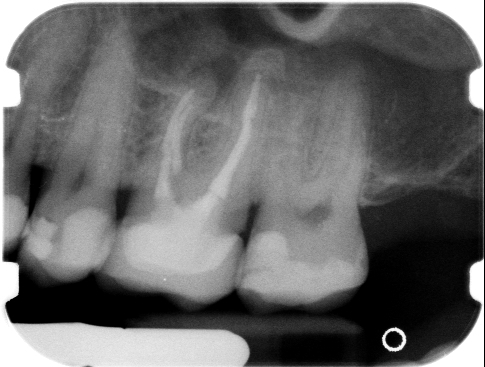

• a contenuto generico (carie, estrazioni dentali, granulomi, ascessi, dolore denti, protesi, impianti, ecc.. ), se non dettagliate nei particolari e, possibilmente, corredate da documentazione ( RX endorali, Ortopanoramiche, immagini fotografiche, ecc... );